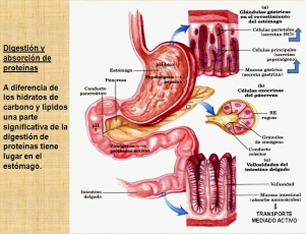

El colon o intestino grueso, es la porción final del tracto digestivo humano. Se encarga de eliminar los desechos del cuerpo. En un colon sano y en condiciones normales, viven bacterias “amigables” que sintetizan valiosos nutrientes como las vitaminas 'K' y partes del complejo “B”.

Cuando la eliminación de lo que el cuerpo no necesita es deficiente, en el colon se acumulan en grandes cantidades que lo obstruyen, creando sustancias nocivas para el buen funcionamiento de los demás sistemas, iniciando el decaimiento del cuerpo, para luego dejar de ser la maquina perfecta.

Los complejos mecanismos por los que actúan estos y otros sistemas, como el digestivo, el respiratorio y el inmunológico, permiten que un cuerpo conserve su estado de salud, gracias al trabajo en equipo ejercido por la unidad funcional básica de nuestro cuerpo: la célula.

El colon, los riñones, los pulmones y la piel, son los responsables de la eliminación de los desechos del cuerpo. El funcionamiento correcto del colon es esencial para mantener una buena salud. Muchos de nuestros problemas crónicos de salud, provienen de una disfunción intestinal.

Un colon lento o que funciona mal, puede perder capacidad para eliminar los residuos del tracto gastrointestinal, debido a una dieta deficiente o inadecuada, la ingesta de tóxicos y el estilo de vida.

El estreñimiento es un estado del intestino en el que las evacuaciones son poco frecuentes y difíciles. La comida no digerida y los residuos pueden permanecer alojados en el intestino grueso durante días, semanas o incluso meses y el colon se puede saturar con toxinas dañinas.

Si esto sucede, a través de un proceso llamado “autointoxicación”, estas sustancias tóxicas pueden ser transportadas al torrente sanguíneo, donde los sistemas linfático y circulatorio, así como los pulmones y los riñones, se sobrecargan y nos exponen a graves riesgos de salud.